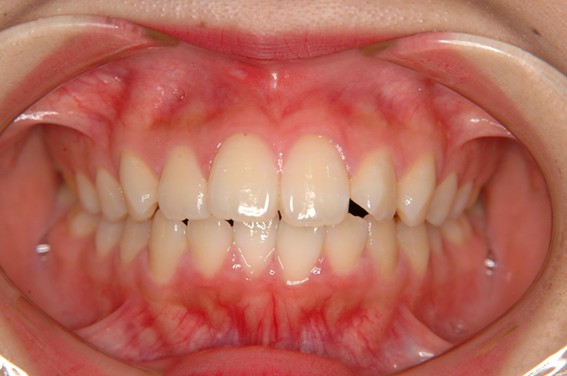

| 主訴 | 口元がでている、口が閉じずらい、上の歯と下の歯のがたつき、顎がない。 |

| 治療内容 | 上下のワイヤー矯正を行いました。 |

以前骨切りを勧められたことがあるという方でしたが、抜歯矯正で口元の突出や顎のしわを改善しました。上唇の厚みや頬の高さを考慮し、老けた印象にならないよう配慮。お顔全体のバランスと年齢に合わせた治療を行いました。